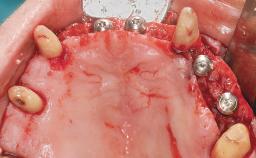

Immediate Loading of Eight Implants in the Maxilla and Six Implants in the Mandible and Final Restoration with Three-Unit and Four-Unit FDPs

Extensive scientific evidence has confirmed that immediately loaded implants with fixed full-arch provisional restorations can osseointegrate with success rates similar to conventionally or delayed loaded implants. A number of immediate-provisionalization techniques for edentulous jaws have been described. Some protocols differ when it comes to prefabricated provisional templates versus complete denture conversion; intrasurgical impressions versus direct relining; and cemented versus screw-retained provisional restorations. In this context, complete-denture conversion has been proposed for either intrasurgical impressions or direct relining. Another possibility is the utilization of a prefabricated provisional to be adapted either in the mouth (by direct relining) or in the laboratory (on a working model obtained from an intrasurgical impression).

Defining Characteristics Fully edentulous upper jaw to be rehabilitated with four or more implants

Modality 6+ implants with immediate loading

Defining Characteristics Fully edentulous upper jaw to be rehabilitated with an implant-borne fixed dental prosthesis

Loading Protocol Immediate